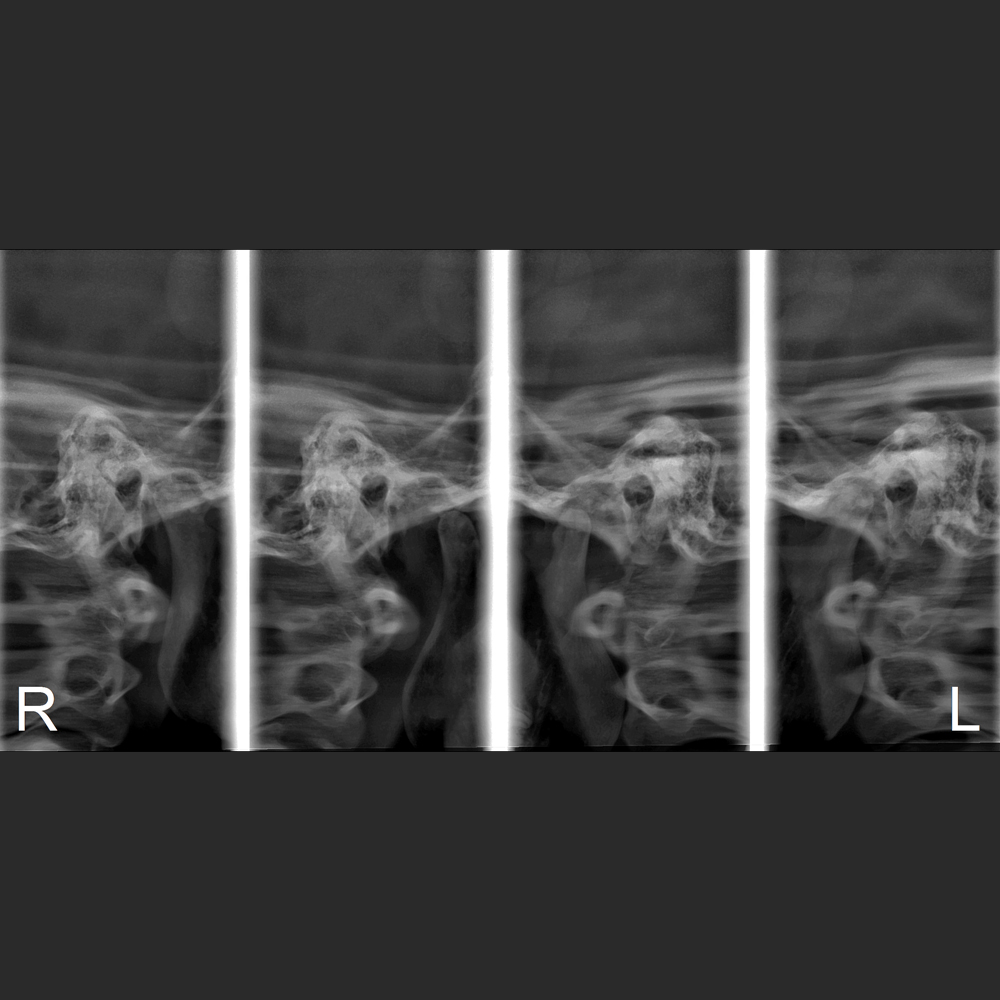

y todos los exámenes en el perfil cefalométrico (Posteroanterior, Antero-posterior, 45 Grados, Lateral, Carpal, PA de Walters, Axial Bazal, Hirtz).